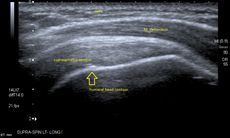

تصوير الكتف

الموجات فوق الصوتية